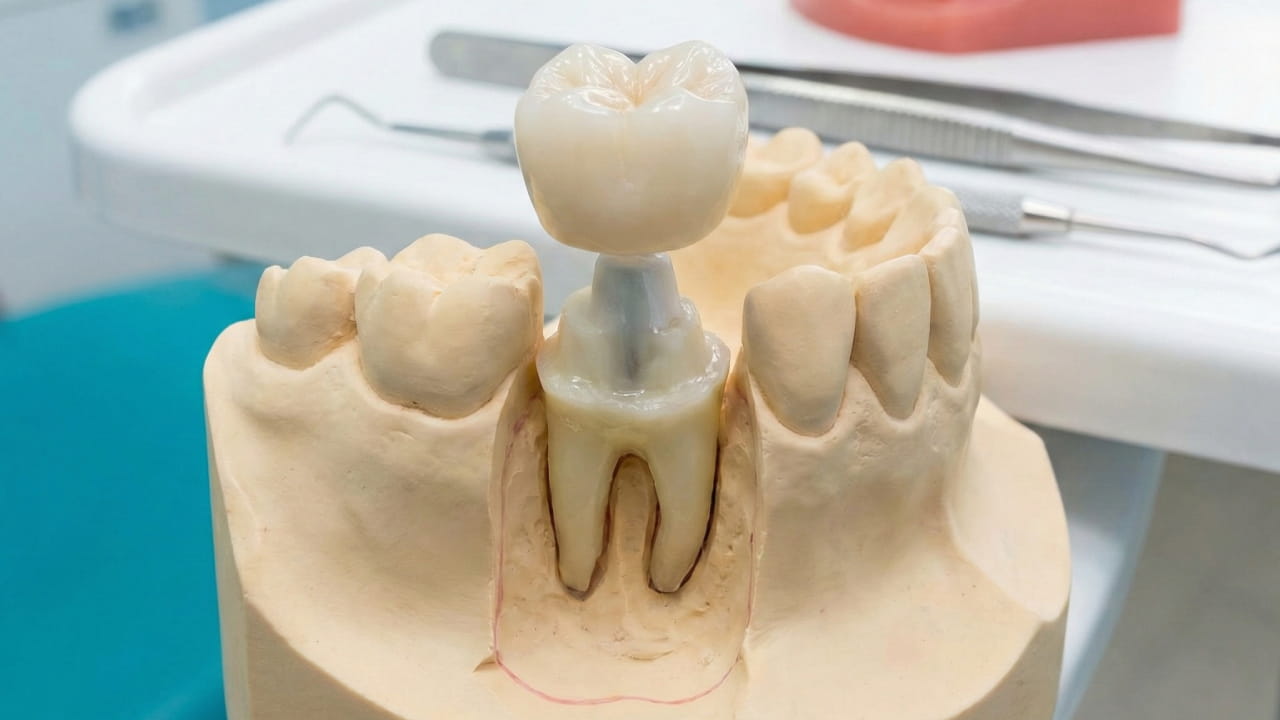

Dental crowns are recommended when a tooth is weakened, damaged, or decayed. They cover and protect the entire visible portion of the tooth, restoring strength, function, and appearance.

How Dental Crowns Help

Crowns restore the strength, function, and appearance of damaged teeth.

Your Step-by-Step Dental Crown Journey

Step 1: Comprehensive Examination

Step 2: Digital Scans & X-Rays

Step 3: Tooth Preparation

Step 4: Impressions & Shade Selection

Step 5: Temporary Crown (If Needed)

Step 6: Permanent Crown Placement

Step 7: Long-Term Aftercare Guidance